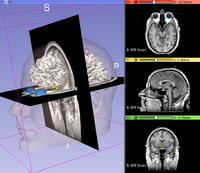

该图展示了如何使用3D Slicer加载DICOM图像,并进行三维可视化。